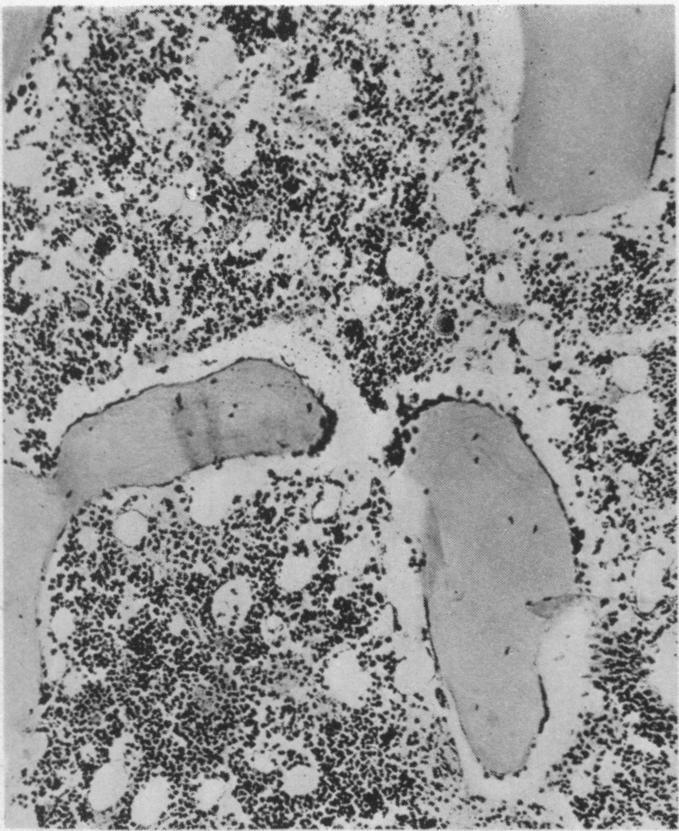

Rheumatoid arthritis in the young.

Br Med J. 1949 Jul 23;2(4620):197-201. doi: 10.1136/bmj.2.4620.197.